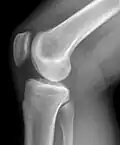

Raio-X de um joelho. -